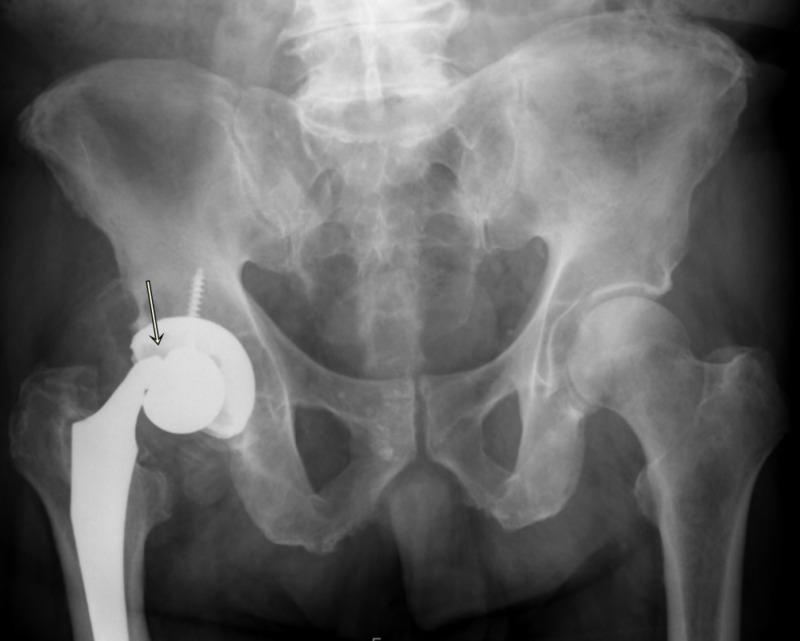

Trunnionosis is a type of corrosion and wear at the head-neck taper junction of the femoral implant, and it can be a slow and silent catastrophe. Simultaneous prosthetic joint infection (PJI) is occasionally possible based on the fulfillment of a few of the minor criteria from the Musculoskeletal Infection Society (MSIS), but the existing literature lacks adequate evidence to support that the infection actually exists. We are presenting a case of an 82-year-old man with right total hip arthroplasty performed over a decade prior to presenting to the emergency room with a sudden-onset pop followed by groin pain and difficulty in walking. Radiographs showed a dissociated femoral implant at the level of trunnion with malalignment and heterotopic ossification. Metal Artifact Reduction Sequence MRI of the right hip showed mixed type-two and type-three pseudotumors, and atrophy of surrounding abductor muscles. The erythrocyte sedimentation rate was within normal limits, C-reactive protein was borderline raised, and serum cobalt-chromium levels were elevated without any signs of systemic metal toxicity. Hip joint aspirate revealed blood-stained fluid flooded with red blood cells, leukocytes and neutrophils, and a positive alpha-defensin assay. These findings were interpreted as positive for prosthetic joint infection. Intraoperatively, there was severe wear of the inferomedial aspect of the femoral head-neck junction and extensive metallosis throughout the right hip. Tissue and fluid specimens were sent for cultures, sensitivities, and histopathology for pseudotumor and infection evaluation. An articulating antibiotic spacer was then placed with the intent to perform a staged reconstruction of the femur and right acetabulum. Final synovial, bone, and soft tissue cultures, as well as histopathological photomicrograph of the tissue slides, were negative for infection. This case demonstrates the striking features of metallosis associated with trunnion failure of a metal-on-polyethylene total hip joint prosthesis that was simultaneously showing signs of prosthetic infection by satisfying the minor criteria according to the latest guidelines by the MSIS with a strikingly high cell count of red blood cells in the synovial fluid exam, indicating inflamed hyper-vascular pseudotumors vs. hemarthrosis vs. bloody tap. Diagnostic dilemma led by positive synovial fluid alpha defensin, high synovial neutrophil and white cell count results with negative final cultures or infection on histological slides raises concern that infection was not present and two-stage revision arthroplasty with six weeks of antibiotics was not necessary along with increased risk of morbidity, mortality as well as cost of care.

股骨柄腐蚀是指股骨植入物头颈锥度交界处的一种腐蚀和磨损情况,它可能是一场缓慢且悄无声息的灾难。根据肌肉骨骼感染学会(MSIS)的一些次要标准,偶尔可能会同时发生人工关节感染(PJI),但现有文献缺乏足够证据支持感染实际存在。我们报告一例82岁男性患者,该患者在十多年前接受了右全髋关节置换术,之后因突然出现的砰的一声响,随后出现腹股沟疼痛和行走困难而前往急诊室就诊。X线片显示股骨柄水平处股骨植入物分离,伴有排列不齐和异位骨化。右髋关节的金属伪影减少序列MRI显示为混合型二型和三型假肿瘤,以及周围外展肌萎缩。红细胞沉降率在正常范围内,C反应蛋白略升高,血清钴铬水平升高,但无任何全身金属中毒迹象。髋关节穿刺抽出的液体为血性,充满红细胞、白细胞和中性粒细胞,α-防御素检测呈阳性。这些结果被解释为人工关节感染呈阳性。术中发现股骨头颈交界处的内下侧严重磨损,整个右髋关节有广泛的金属沉着症。将组织和液体标本送去进行培养、药敏试验以及用于假肿瘤和感染评估的组织病理学检查。然后放置了一个可活动的抗生素间隔物,打算分阶段重建股骨和右髋臼。最终的滑膜、骨和软组织培养结果,以及组织切片的组织病理学显微照片显示感染为阴性。该病例展示了与金属对聚乙烯全髋关节假体股骨柄失效相关的金属沉着症的显著特征,根据MSIS的最新指南,该病例同时通过满足次要标准显示出人工感染的迹象,在滑膜液检查中红细胞计数极高,提示为炎症性高血管假肿瘤与关节积血与血性穿刺的区别。滑膜液α-防御素阳性、滑膜中性粒细胞和白细胞计数高且最终培养结果或组织学切片感染为阴性所导致的诊断困境,引发了人们对感染是否存在的担忧,以及六周抗生素治疗的两阶段翻修关节成形术是否必要,同时还增加了发病、死亡风险以及护理成本。